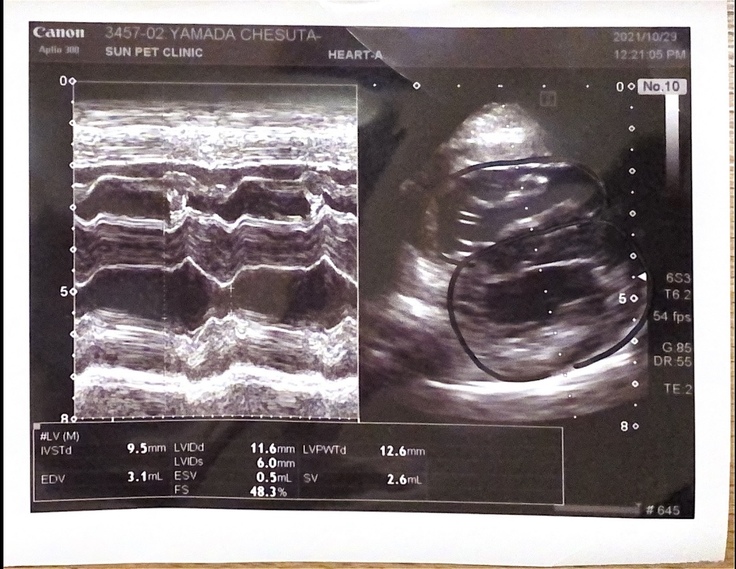

↓先生が描いてくれた心臓のイラスト

↓黒いペンで描かれている丸のうち、上側(イラストでいう右)のサイズが左と変わらないくらいになってしまっている